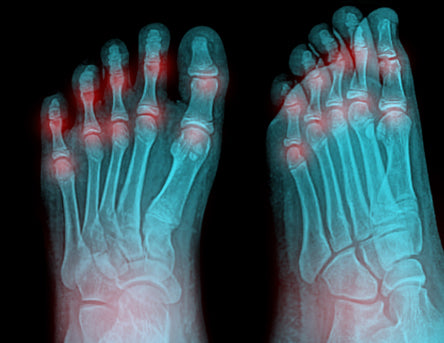

There are different types of arthritis which commonly affect the foot or ankle, including osteoarthritis, rheumatoid arthritis and gout. Arthritic pain can range from mild to severe. Each type of arthritis can cause different symptoms, but in all of them inflammation is a factor. Osteoarthritis is a common type of joint disease, also called degenerative joint disease or “wear and tear” arthritis in which cartilage between joints breaks down leading to swelling, stiffness, and pain. Rheumatoid arthritis is an autoimmune disease which causes painful swelling in the joint lining and eventually causes joint erosion and bone deformity.

Gout is a very common form of arthritis which differs from the other types and is usually noticed with the sudden onset of pain in the joint of the big toe.